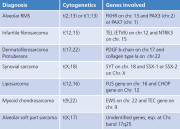

| 10:39, 12 באוגוסט 2023 | Sarcoma 1.png (קובץ) |  |

94 קילו־בייטים | Motyk | 1 | |